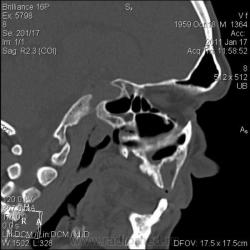

КТ головного мозга. Случайная находка. Жалоб "на челюсти" нет.

Мужчине 51 год. Периферический рак легкого. Очаговых изменений головного мозга не нашла. Пациент не критичен к своему состоянию (никуда не поеду, пусть как есть остается), поэтому отсутствие жалоб еще ничего не значит.

Контуры внутренние деструктивной полости изъеденные, кость вздута, но внешне не видно. В центре уровень?  с плотностью 30 ед.Н. Адамантинома? С зубными делами практически не сталкиваюсь. Нужна Ваша помощь. Какие будут идеи, уважаемые коллеги?